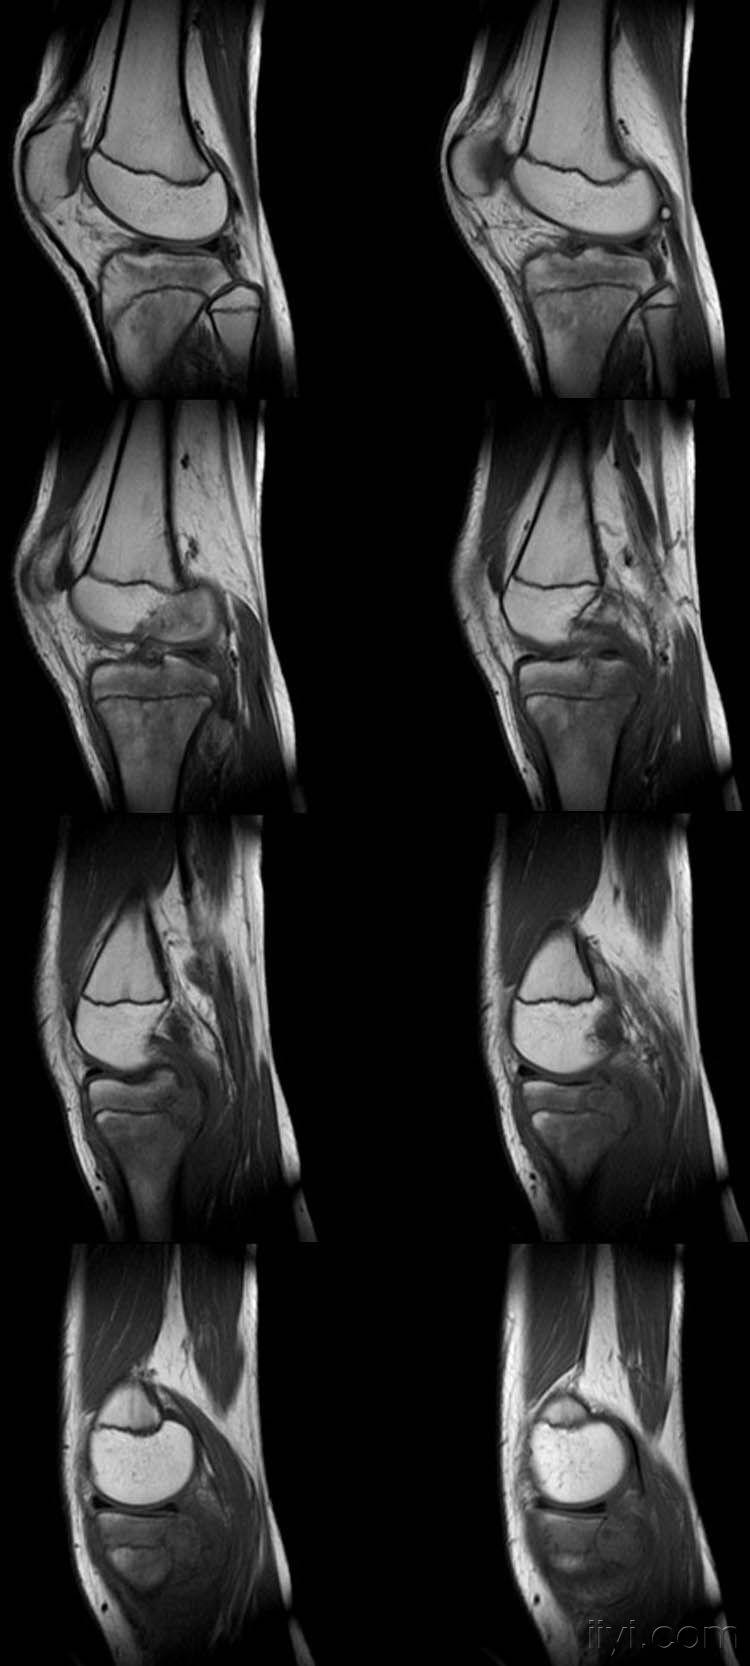

女,14岁,膝关节外伤后疼痛4月余。

向老师学习,恶性肿瘤可能,骨肉瘤?